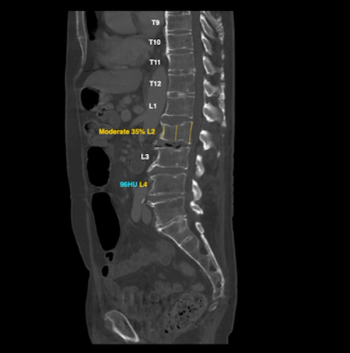

The AI-enabled CINA-VCF algorithm can reportedly detect vertebral compression fractures within seconds after assessment of chest or abdominal CT scans.